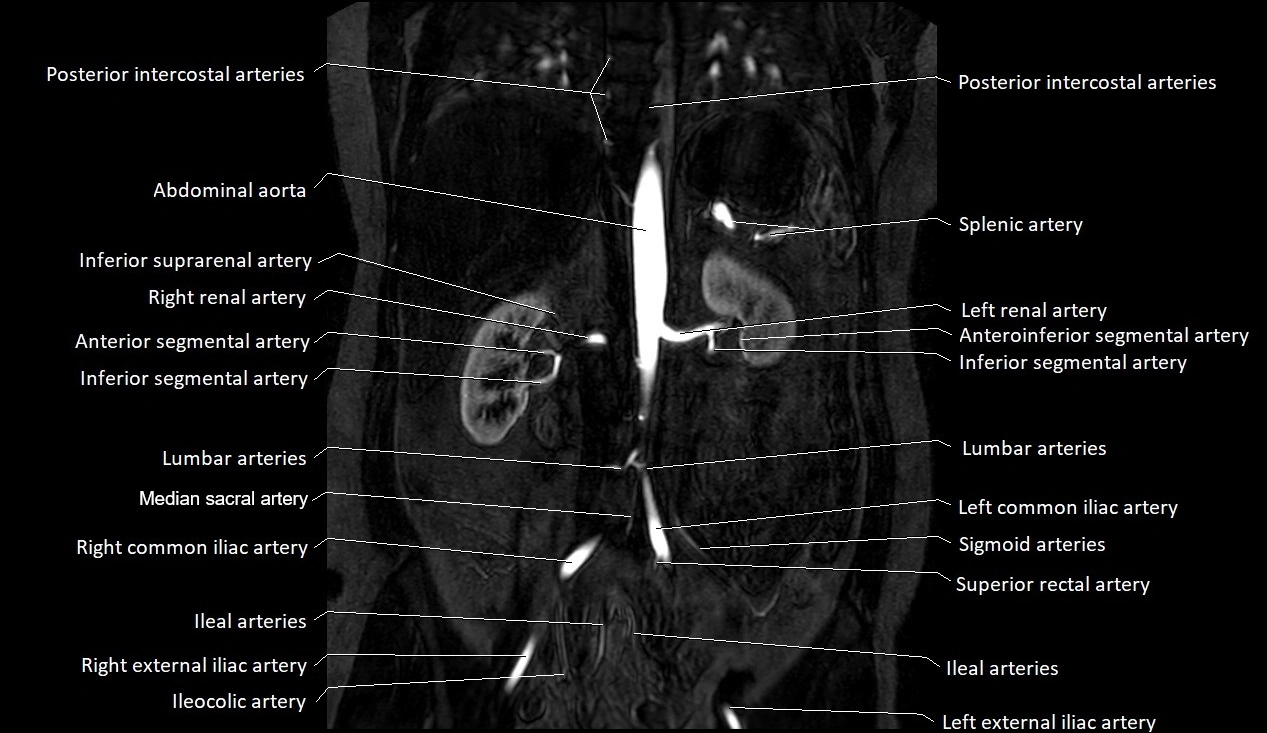

MRA (Magnetic Resonance Angiography):

• Contrast-enhanced MRA provides high-resolution imaging of the aorta and its branches

• Allows 3D reconstruction of visceral, parietal, and terminal branches

• Excellent for evaluating aneurysm size, dissection flap, stenosis, or preoperative planning

• Non-invasive alternative to conventional angiography

MRI images

image